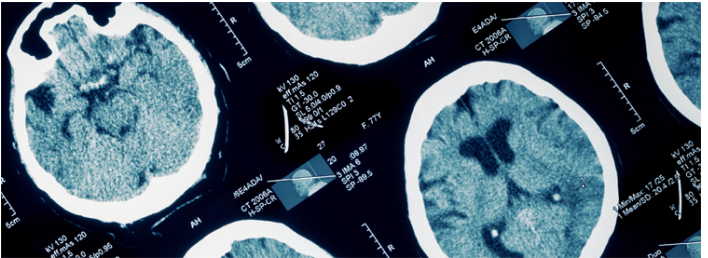

뇌병변장애를 이해하려면 먼저 이것이 '뇌손상(Brain Injury)'이라는 점을 명확히 알아야 합니다. 여기서 뇌손상이란 뇌 조직의 특정 부위가 손상되어 정상적인 신호 전달과 기능 수행이 어려워진 상태를 의미합니다. 제가 직접 전문의와 상담하면서 배운 것은, 이 손상이 발생한 시기와 위치에 따라 증상이 천차만별로 나타난다는 사실이었습니다.

많은 분들이 뇌병변장애를 증상 중심으로만 이해하려고 하는데, 실제로는 그 원인인 뇌손상 자체를 이해하는 것이 훨씬 중요합니다. 신경가소성(Neuroplasticity)이라는 개념이 있습니다. 이는 뇌가 손상된 부위의 기능을 다른 부위가 대신 학습하여 보완할 수 있는 능력을 말합니다. 특히 어린 나이일수록 이 신경가소성이 뛰어나기 때문에, 조기 개입이 그토록 강조되는 겁니다.